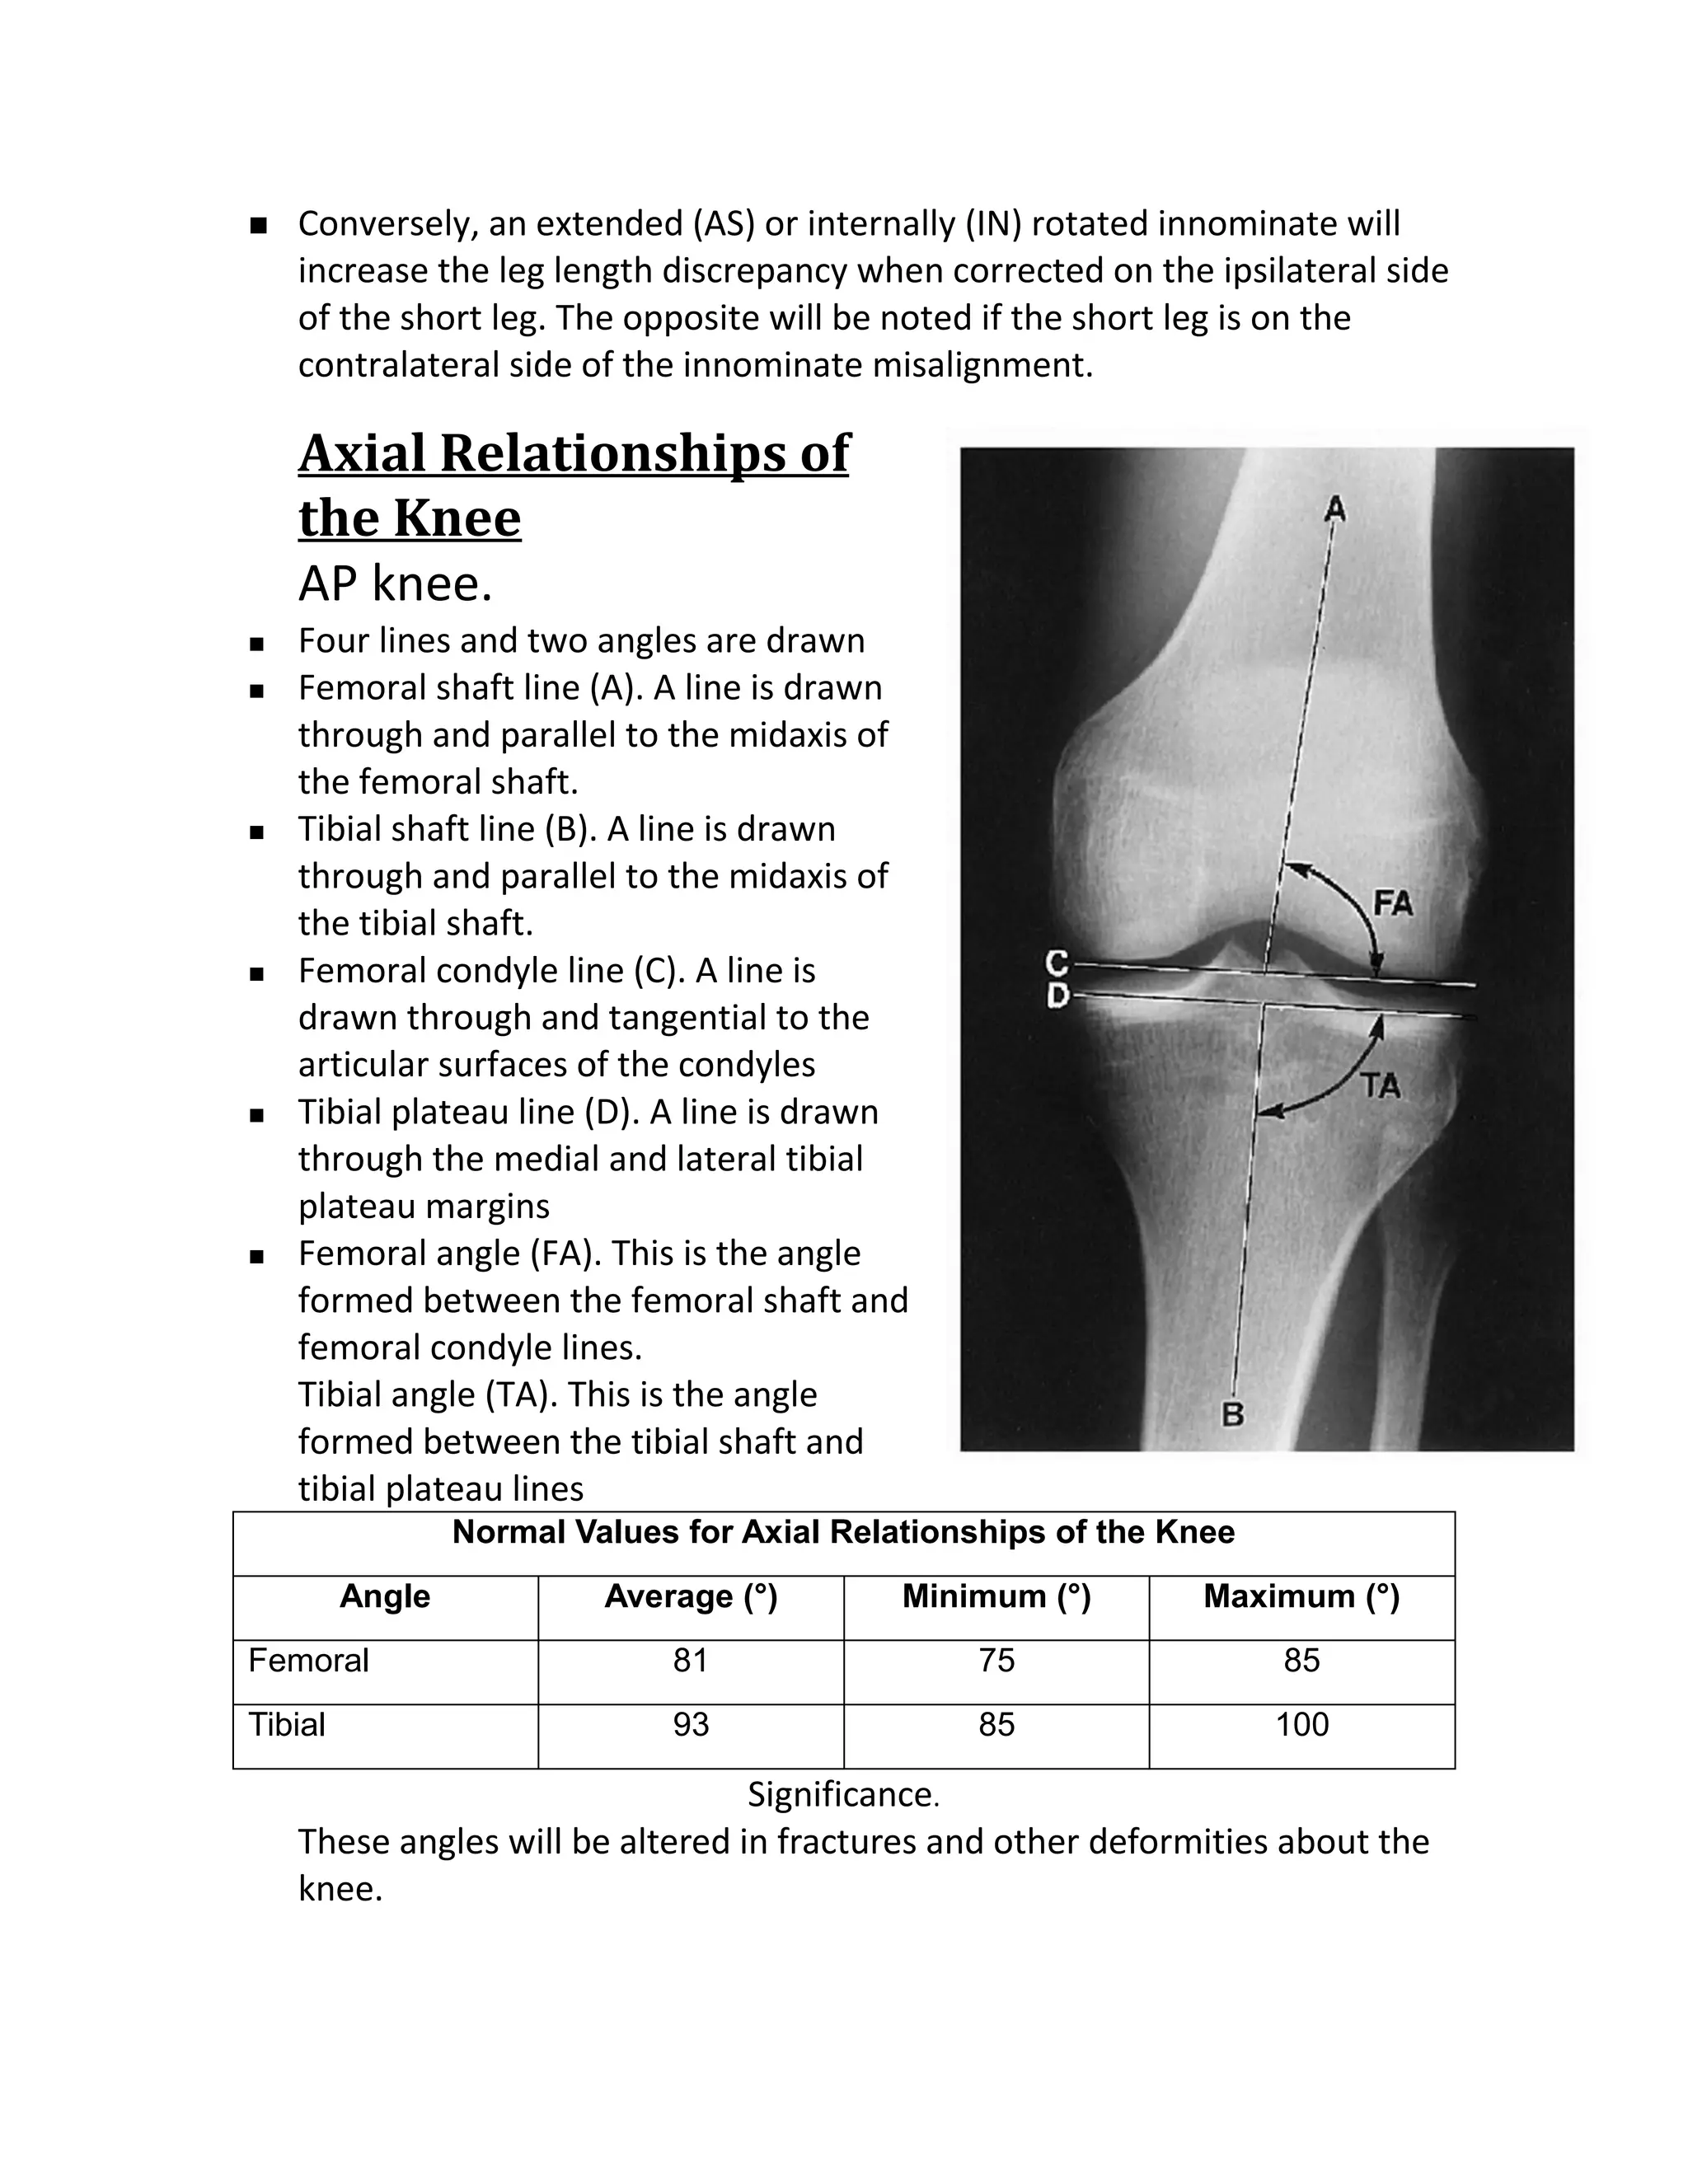

Axial Relationships of

the Knee

AP knee.

   Four lines and two angles are drawn

   Femoral shaft line (A). A line is drawn

through and parallel to the midaxis of

the femoral shaft.

   Tibial shaft line (B). A line is drawn

the tibial shaft.

   Femoral condyle line (C). A line is

drawn through and tangential to the

articular surfaces of the condyles

   Tibial plateau line (D). A line is drawn

through the medial and lateral tibial

plateau margins

   Femoral angle (FA). This is the angle

formed between the femoral shaft and

femoral condyle lines.

Tibial angle (TA). This is the angle

formed between the tibial shaft and

tibial plateau lines

Normal Values for Axial Relationships of the Knee

Angle            Average (°)        Minimum (°)       Maximum (°)

Femoral                       81                 75                  85

Tibial                        93                 85                  100

Significance.

These angles will be altered in fractures and other deformities about the

knee.